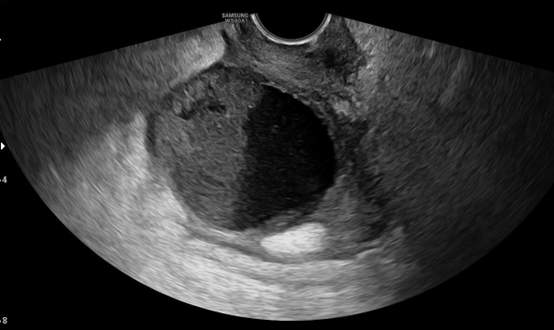

近日,延安市中医医院(北京大学第三医院延安分院)妇科收治了一位64岁患者。患者因不洁饮食后,出现间断性下腹坠胀痛,憋尿时疼痛加剧,且伴有里急后重、恶心呕吐、腰困、尿频尿急及发热症状。曾在多家诊所及外院接受抗感染治疗,然而腹痛却愈发严重,遂紧急来我院就诊。入院检查显示患者血象偏高,肝酶异常。超声检查发现,患者子宫后方偏左侧有一约7.5*5.0cm的混合回声包块;查体时,在子宫直肠窝触及一约7cm*5cm的质硬包块,触痛明显,下腹压痛强烈。

刘娜主任与北医三院驻延专家宋菁华教授带领团队迅速响应,共同为患者诊疗,经详细检查,初步判断为盆腔脓肿。住院期间,患者持续高热39.2℃,经多学科会诊评估后,密切监测生命体征,联合超声医学科为患者实施超声引导下盆腔脓肿穿刺引流术,成功引出脓液190ml,手术顺利。术后包块明显缩小,患者自觉症状缓解。穿刺术后1周复查,包块缩小至约3.3cm*2.0mm。后续结合中药口服、灌肠及外敷等中医特色治疗,现患者恢复良好,已顺利出院。